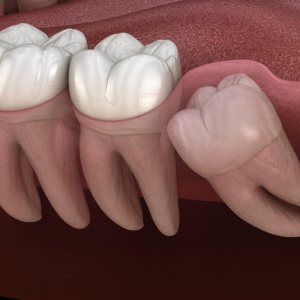

Khi nào cần nhổ răng khôn? Dấu hiệu răng khôn mọc lệch, mọc ngầm

Răng khôn mọc lệch: Dấu hiệu, nguyên nhân, cách xử lý